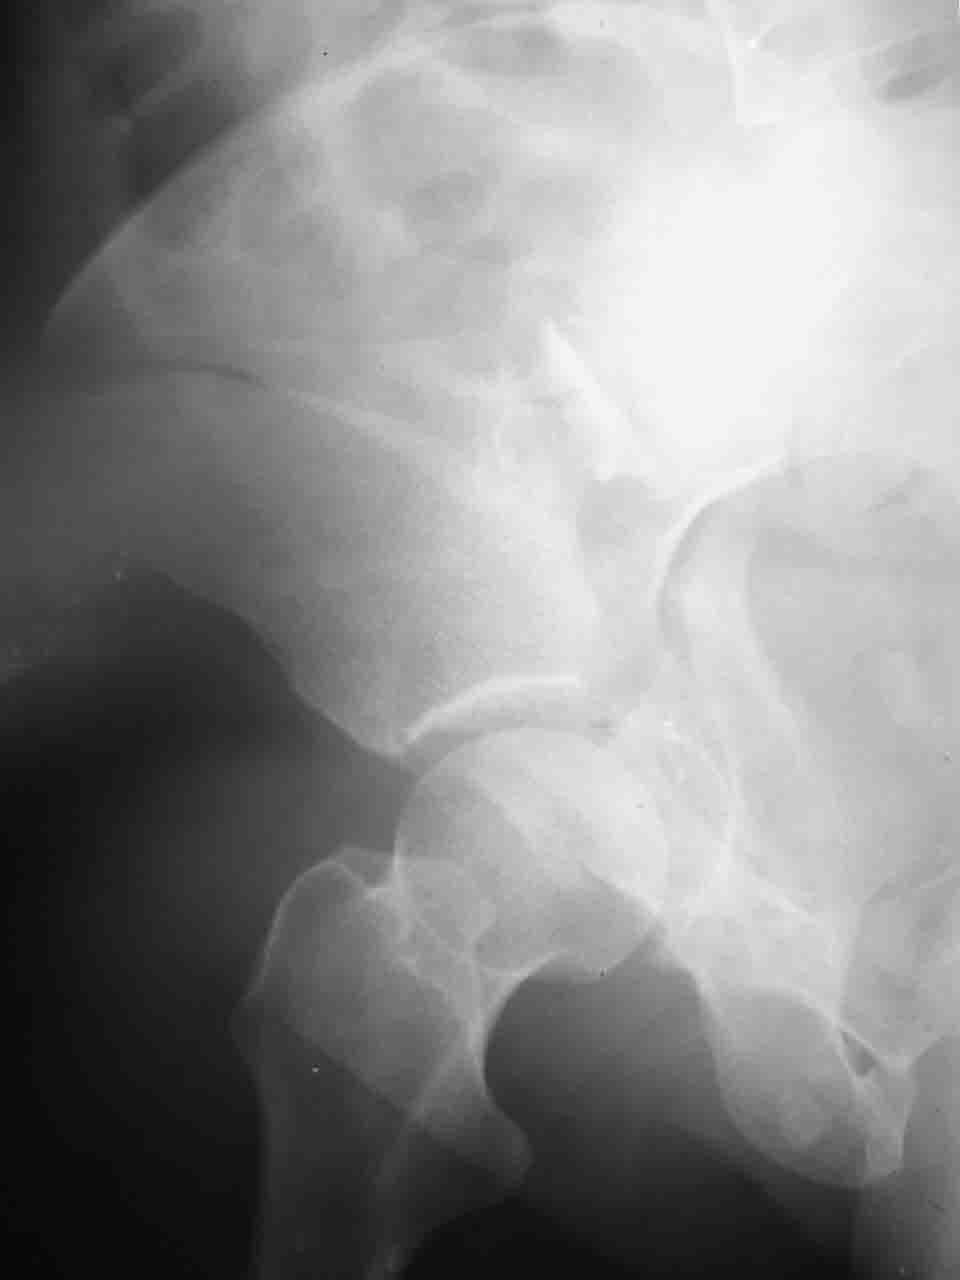

Уважаемые коллеги,43 летний мужчина, попав в автоаварию 13.10.2004, получил оскольчатый перелом обеих колонн левой вертлужной впадины.

На рентгенограммах - высокий двухколонный перелом вертлужной впадины с нарушением конгруэнтности, имеется обратная клиновидность суставной щели.

Спасибо за комментарии и рекомендации. Откровенно говоря, больного я прооперировал на прошлой неделе, через 5 дней после аварии и проблем с ним пока никаких нет, на удивление при достаточно обширной диссекции (илиофеморальный доступ) болей практически нет, так что больной самостоятельно садится в кровати, выполняет активные движения в оперированном суставе, сгибая до 60 градусов пока, далее с ассистенцией.

Причиной обращения к сообществу были возникшие непосредственно после операции сомнения и разочарования полученным качеством репозиции: а надо ли было трогать перелом вообще, репозиция передней колонны технически была очень сложна для меня, хотя реконструкции была в той же последовательности, что Д-р А.В.Рунков рекомендовал, в какой-то момент безуспешных манипуляций стал думать о *вторичной конгруэнтности*, которую не так давно обсуждали на

форуме и скелетном вытяжении. С репозицией и фиксацией задней колонны и отдельно задне-верхней стенки впадины проблем не возникло. Послеоп. Рг граммы в приложении. Если возникнут какие-либо дополнения или поправки - был бы признателен.